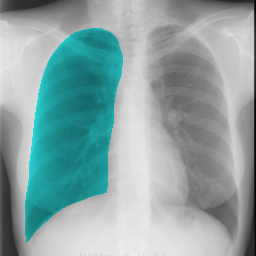

The task of chest organ segmentation is a simple benchmark task in medical image segmentation. In this task, we consider three semantic classes, namely left lung, right lung, and heart. We can easily control the environment to get an insight into the impact of the limited partial labels on various representative partially supervised methods and the efficiency of VLUU. Without specification, the experimental comparison is conducted in such a way that different models use the same network backbone, loss function, training strategy, and the set of hyperparameters.

We use three partially labeled datasets as the training set and one fully labeled as the test set, where the four datasets are collected from four different sources. We choose this setup to simulate the practical scenarios where dataset shift exists, which is a challenging situation for DL models. We use the JSRT dataset as the left lung dataset, denoted as L. We use a subset of the Wingspan dataset containing 18 CXRs as the right lung dataset, denoted as R. We use another subset of the Wingspan dataset containing 18 CXRs as the right lung dataset, denoted as H. We use the rest of the Wingspan dataset as the fully labeled test set, which contains 185 CXRs, and denote it as T. The visual comparison of the data modalities of the four sets can be viewed in Fig. 5. Note, all four sets are collected from 4 different sources (hospitals with different imaging protocols).